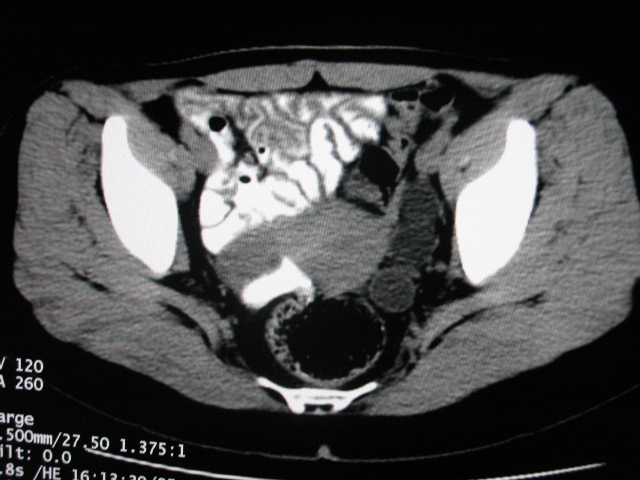

女,28岁,自觉腹部包块一年余

左侧为扩张的输尿管,一直延续到膀胱,那么它的上端应该是扩张的肾盂,但是在他的下方我们看到一个比较正常的肾,所以考虑左侧重复肾盂输尿管畸形。

考虑左侧双肾盂双输尿管畸形,其中一输尿管末端梗阻(不排除异位开口可能)并相应之肾盂及输尿管明显扩张积水。

考虑左侧双肾盂双输尿管畸形,其中一输尿管末端梗阻并输尿管肠管样扩张盂曲、肾盂囊状扩张积水。

术后证实是左侧双肾盂双输尿管畸形,巨输尿管巨肾盂症